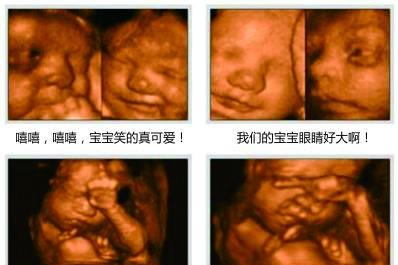

王祖蓝晒女儿四维照片,胎宝宝四维照片这么丑,你能接受吗